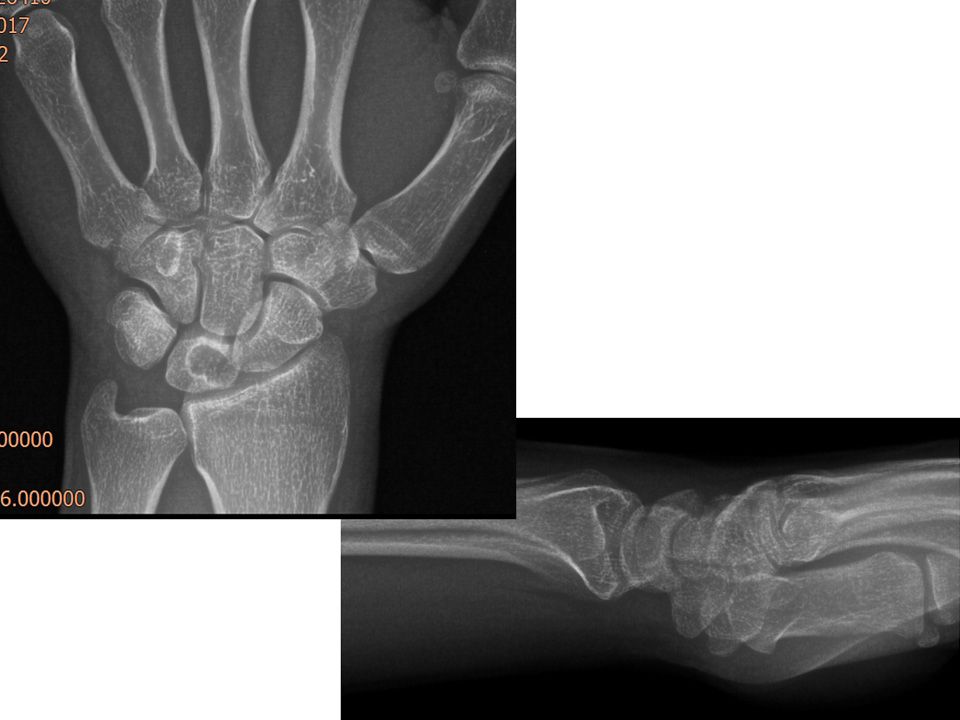

Case 04 - Intraosseous Ganglion Cyst of The Lunate 33 yr, male, warehouse worker, right hand dominancyPain at scapholunate jointRight wrist extension 50°, flexion 60°Watson shift test -